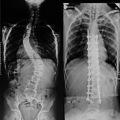

Fotos